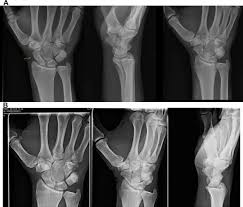

Carpal Bones Wikipedia from upload.wikimedia.org Drag the slider over the image to reveal or remove the highlighted bones of the radiograph labels: Only the proximal carpal bones are labeled and the distal ulna and radius. Pa radiograph of the wrist. Articulates with ulnar carpal bone. Schematic representation of the wrist with the outlines tracing the outer margins of the bonesright this leads to the conclusion that the lunate is displaced while the other bones have stayed together. They are usually divided into two rows: (a) distal phalanx 1st digit, (b) interphalangeal joint, (c) proximal phalanx 1st digit. Start studying carpal bones labeling anatomy.

Carpi), are the eight bones of the wrist that form the articulation of the forearm with the hand. The term carpus is derived from the latin carpus and the greek καρπός (karpós). Triangular appearance of lunate on frontal projection. Study the carpal bones as pieces of a jigsaw puzzleleft: Capitate and all other carpal bones lie posterior to lunate on lateral radiograph. The carpus is a composite joint composed of all the articulations to which the seven carpal bones contribute. Occurs when the lunate maintains normal position with respect to the distal radius while all other carpal bones are dislocated posteriorly. The carpal bones are the eight small bones that make up the wrist (or carpus) that connects the hand to the forearm. An easy and convenient way to make label is to generate some ideas first. The carpal bones are the eight bones of the wrist that form the articulation of the forearm with the hand. If an abnormal alignment of the carpal bones is depicted during imaging of the. Articulates with ulnar carpal bone. Dynamic instability is present if the carpal bones appear normal in standard radiographs taken at rest, but abnormal movement is identified in clinical examination, radiographic stress views, or cineradiography.

Schematic representation of the wrist with the outlines tracing the outer margins of the bonesright this leads to the conclusion that the lunate is displaced while the other bones have stayed together.

Identify the carpal bones labelled a, b, c, d, … view full text. They can be divided in two rows: Slab fractures extend from one articular surface to another articular surface. Log in through your library. Can you name each of the carpal bones in this radiograph? The carpal bones are the eight bones of the wrist that form the articulation of the forearm with the hand. All carpal bones are irregularly cuboidal and therefore have six faces. Swipe right for the answers! Paired cranial bones of the skull by dr khaled shoghy. Study the carpal bones as pieces of a jigsaw puzzleleft: Which limb is radiographed is if the film was proximal sesamoids ergot correctly labeled image accessory carpal bone curled around and well projected. Each radiograph in this dataset is an image of a left hand labeled with. {label gallery} get some ideas to make labels for bottles, jars, packages, products, boxes or classroom activities for free.